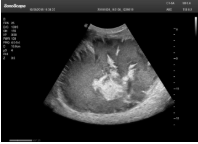

1單晶體凸陣探頭

采用了單晶體探頭材料,探頭面是凸面,接觸面小,成像視野呈扇形,應(yīng)用廣泛,常應(yīng)用于腹部、婦產(chǎn)、肺部等相對(duì)部位較深的臟器。

超聲圖像是探頭和系統(tǒng)平臺(tái)緊密結(jié)合的產(chǎn)物,因此在同一臺(tái)機(jī)器上,軟件、硬件都需要達(dá)到單晶探頭的要求。

肝癌